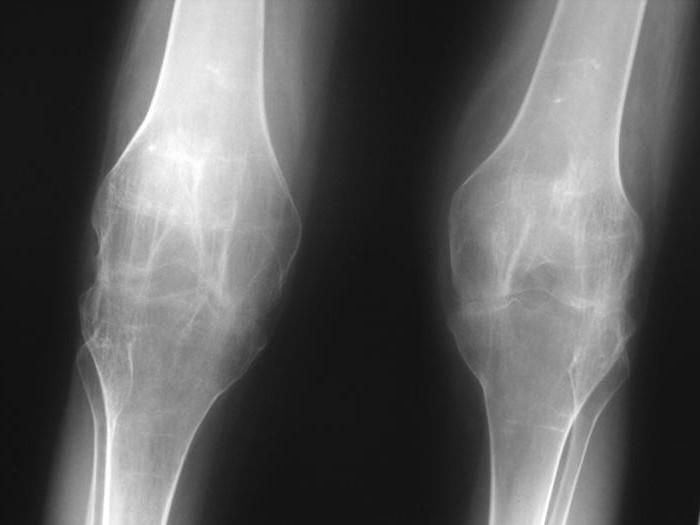

Рентгеновские снимки анкилоза суставов: Как это выглядит